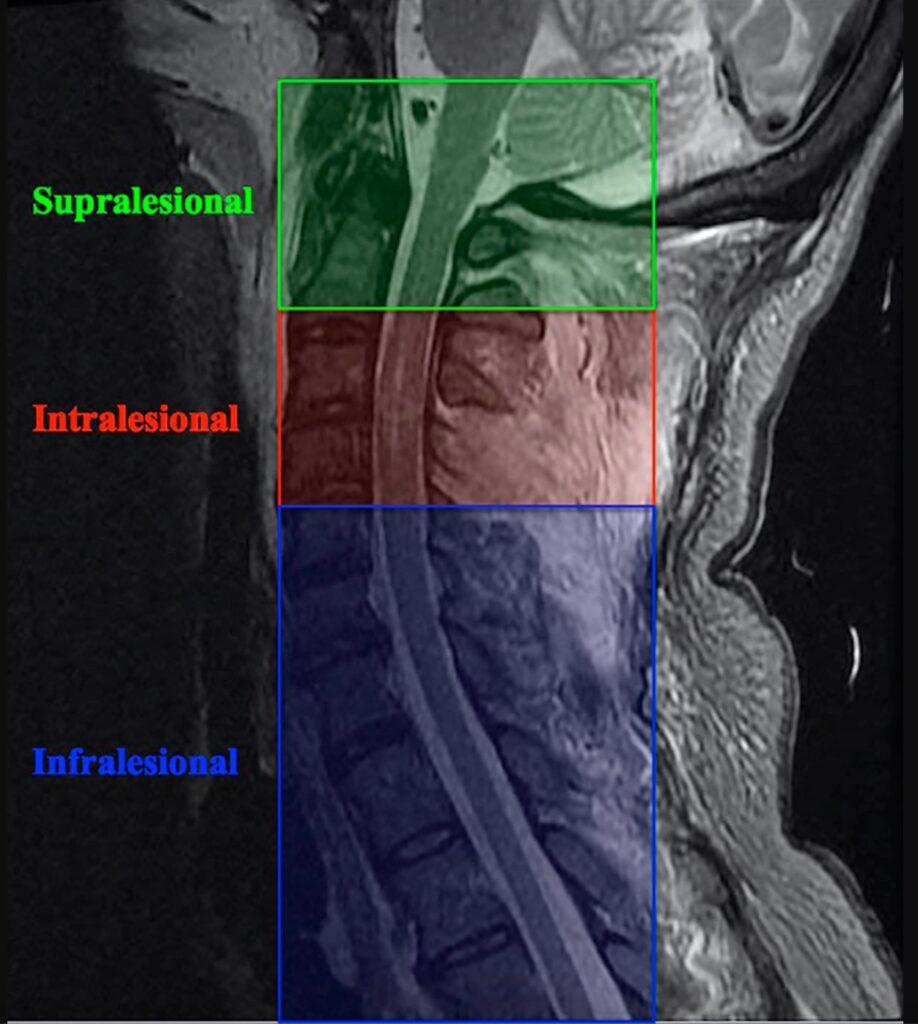

»La toma de decisiones quirúrgicas para la reconstrucción de las extremidades superiores en pacientes con tetraplejia se basa en un examen físico completo para determinar qué nervios y músculos permanecen bajo control volitivo con la fuerza adecuada para la transferencia.